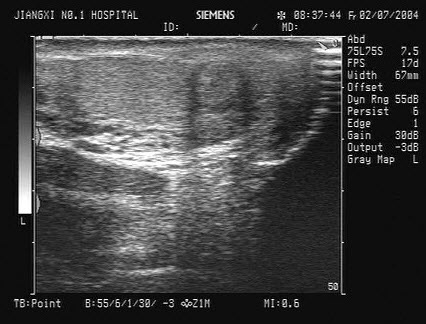

53、单项选择题

某患者25岁,高热,肝区疼痛。肝脏声像图表现如图,结合病史,最可能的诊断是()